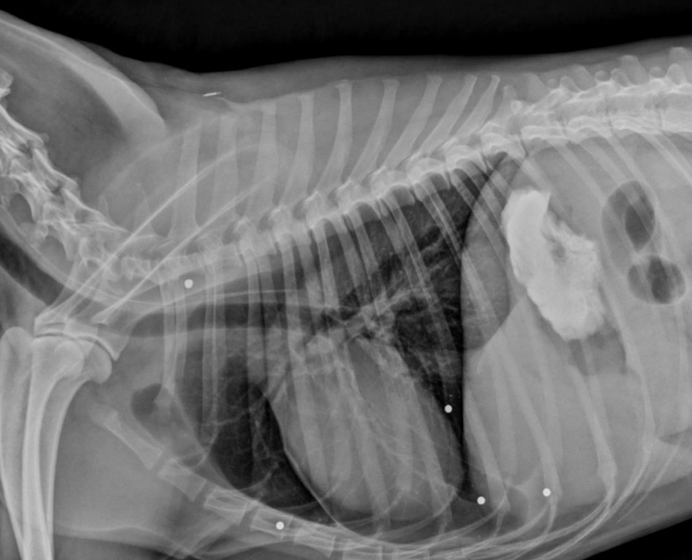

Juvenile idiopathic megaesophagus